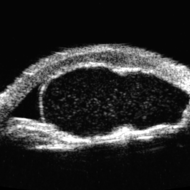

Idiopathic Iris Cyst

Oct 25 2023 by Virginia Gebhart

UBM of recurring idiopathic iris cyst in 72 year old female

Photographer: Virginia Gebhart

Imaging device: Ellex Eye Cubed

Condition/keywords: anterior chamber, cyst, immersion ultrasound, iris